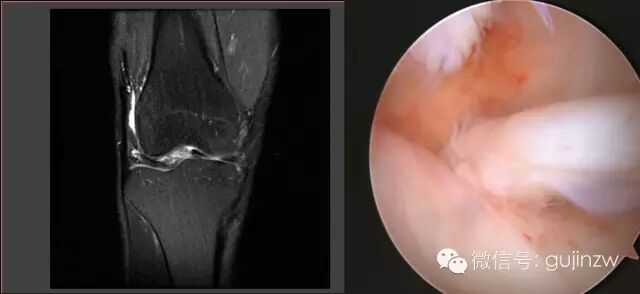

病例2

• 男,24岁。

• 主诉:打羽毛球扭伤致右膝关节疼痛活动受限1天。

• 症状:右膝关节疼痛,活动受限,交锁,伴弹响。

• 体征:膝关节活动度:15-120度,浮髌试验弱阴性,内外侧关节间隙无压痛。

• 被动挤压:麦氏征(+),Apley征(+)。

• 主动挤压:Ege‘s征(+),Thessaly 20°征(+)。

MRI